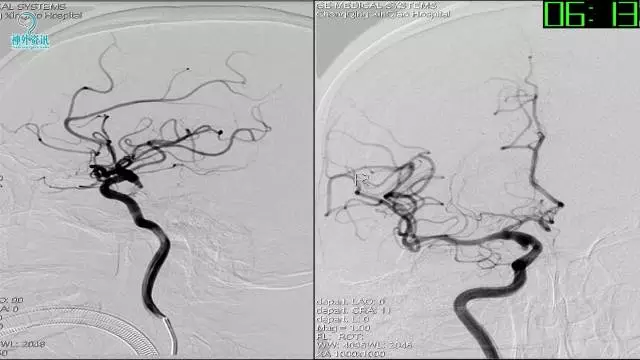

今天为大家分享的是“强生医疗CNV-神经介入专栏”第三十六期,由重庆第三军医大学附属新桥医院神经外科刘俊带来的“Galaxy弹簧圈在不规则动脉瘤中的临床应用”精彩讲课视频及PPT,欢迎观看。文章仅代表作者个人观点,如有不同见解,欢迎同道斧正!